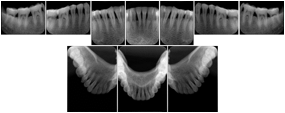

OO.1.2 Ophthalmology

1. A patient in rural Canada visits a general ophthalmologist and is found to have diabetic macular edema. The general ophthalmologist would like to discuss the case with a retina specialist before performing laser surgery. A fluorescein angiogram is done with multiple retinal images taken in a timed series after an intravenous injection. The images along with a Structured Display are shared via a Health Information Exchange with a retina specialist in Calgary, who opens them using his Ophthalmology EMR software and consults via phone with the general ophthalmologist. Both physicians view the images in the same layout so the retina specialist can provide accurate guidance for treating the patient.

2. A patient in rural Iowa visits his primary care physician for management of diabetes. Three non-mydriatic (patient's eyes are not dilated) photographs are taken of the back of each eye, and forwarded electronically along with a Structured Display to an ophthalmologist in Iowa City. The ophthalmologist reads the photos in an agreed upon layout so there is no mistake about what portion of which eye is being viewed. The ophthalmologist is able to tell the primary care physician that his patient does not need to come to Iowa City for face to face ophthalmologic care, but that there is a particular view of the left eye that should be photographed again in 6 months.

Ophthalmic Retinal Study Structured Display

Figure OO-3. Ophthalmic Retinal Study Structured Display

3. A patient in rural Minnesota experiences sudden vision loss and goes to a general ophthalmologist, who acquires OCT images and forwards them electronically along with a Structured Display to a retina specialist six travel hours away. The retina specialist is able to view the images in the standard layout that he is comfortable with, and to confirm that the patient has a choroidal neovascular membrane. He determines that is would be worthwhile for the patient to travel for treatment.

OCT Retinal Study with Cross Section and Navigation Structured Display

Figure OO-4. OCT Retinal Study with Cross Section and Navigation Structured Display